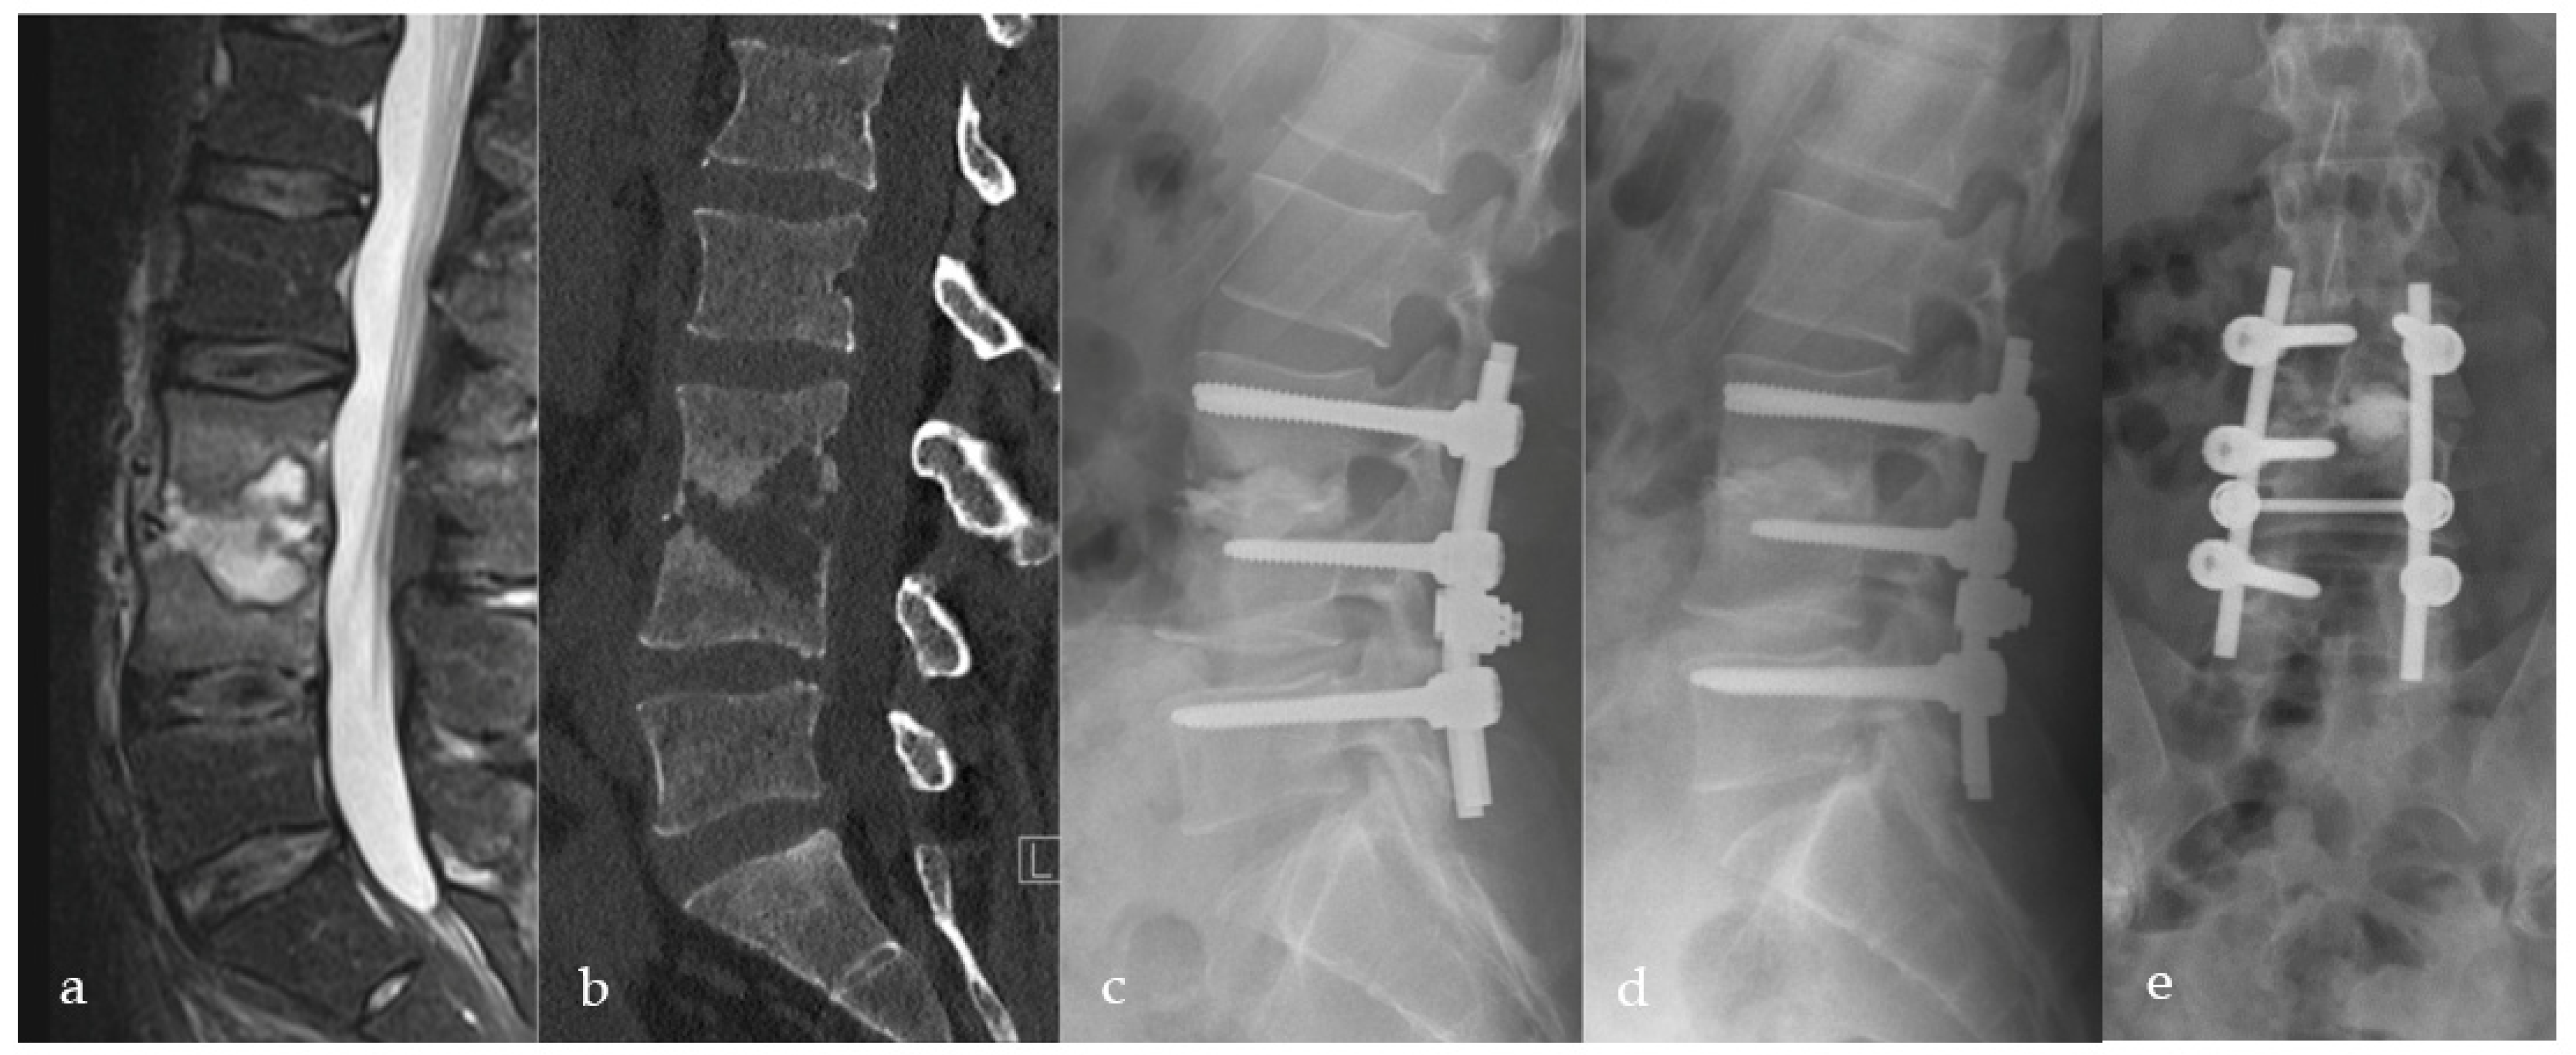

2.2. Surgical Procedure